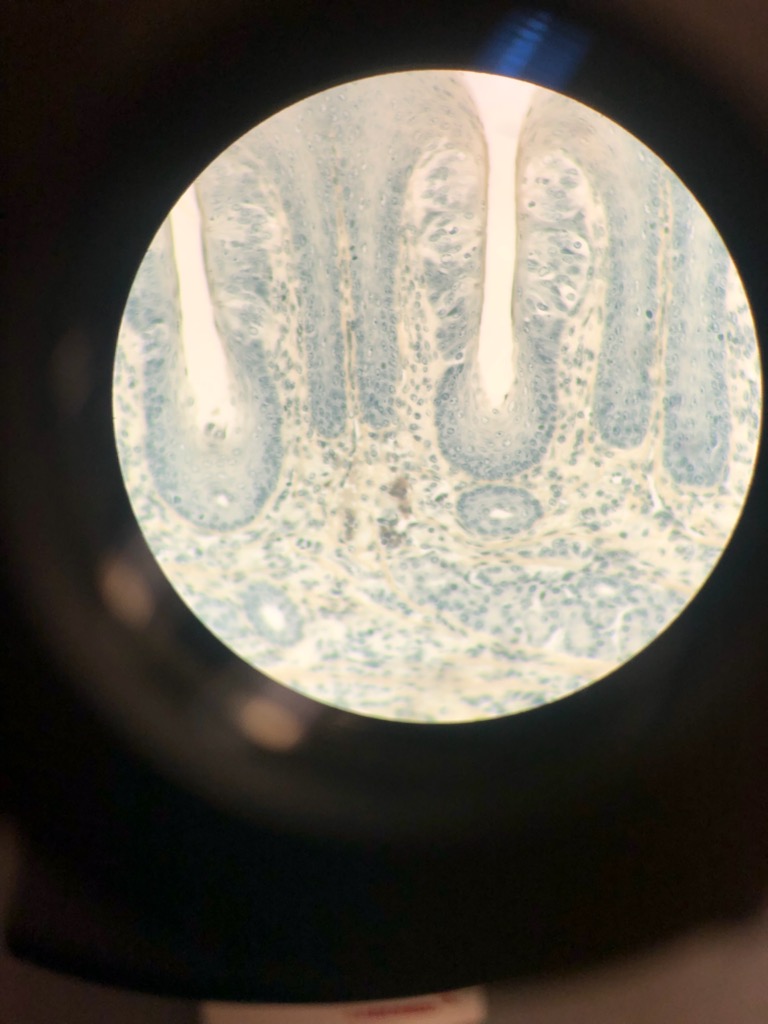

From www.alamy.com

rabbit,taste buds papillae across 100x Stock Photo Alamy Do Rabbits Have Taste Buds Organs of taste — gustatoreceptors (tongue) 3. The sense organs or receptor organs of rabbit are essentially similar with that of the frog except in some details. Organs of touch — cutaneous (skin) receptor. The changes in the environment are known as stimuli. They can distinguish between sweet, sour, bitter and. We know this because rabbits do not have the. Do Rabbits Have Taste Buds.

From etc.usf.edu

Taste bud Cells of a Rabbit ClipArt ETC Do Rabbits Have Taste Buds We know this because rabbits do not have the tapetum lucidum that nocturnal animals have. The sense organs detect the changes in the external and internal environments. There are two structures on the tongue that carry taste buds: The rabbit has 17,000 taste buds situated in the mouth and pharynx. The sense organs or receptor organs of rabbit are essentially. Do Rabbits Have Taste Buds.

Taste bud of Rabbit ClipArt ETC Do Rabbits Have Taste Buds The various sense organs of rabbit are: The rabbit has 17,000 taste buds situated in the mouth and pharynx. Organs of taste — gustatoreceptors (tongue) 3. We know this because rabbits do not have the tapetum lucidum that nocturnal animals have. They can distinguish between sweet, sour, bitter and. We know that rabbits have extra taste buds compared to humans.. Do Rabbits Have Taste Buds.